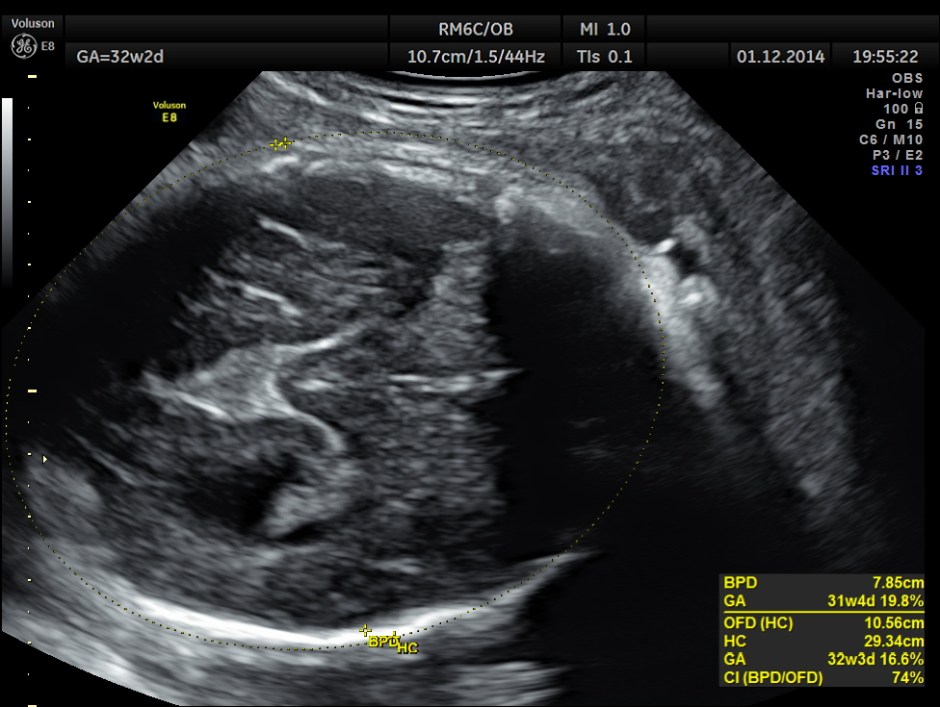

This was a 30 year old lady , with history of consanguinity ; 2nd gravida , 1st child normal ; she has never gone for an ultrasound examination in this pregnancy and was sent by her consultant to a different centre for evaluation . She was found to have hydrocephalus and was referred to our clinic for 2nd opinion.

The following images were obtained.

Hydrocephalus is seen ; Cisterna magna appeared somewhat compressed.